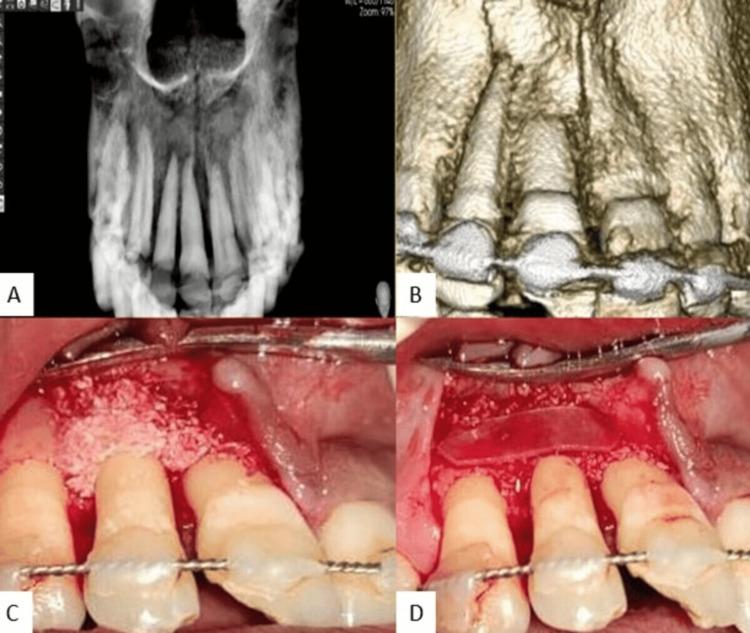

The current case report presents a case of a road traffic accident comprising dental avulsion of maxillary incisors. A 30-year-old male reported missing teeth following trauma in his upper front tooth region. The avulsion of maxillary right central and lateral incisors along with laceration in upper and lower lips was evident. The avulsed teeth were stored in milk after a brief extra-oral dry time of one hour and were carried to the department with a one-hour delay. After clinical and radiographic investigations, no mobility or fractures were apparently noticed. The avulsed 11 and 12 had closed apices with intact crown and root surfaces. Following an extra-oral endodontic therapy, immediate replantation was scheduled. Subsequently, the alveolar sockets were irrigated with saline to dislodge the clot and any gross debris that was present. Teeth were reimplanted into the socket after placement of PRF membrane around the root surface. A semi-rigid wire and composite splinting were done for a span of two weeks and antibiotics were prescribed. An exploratory CBCT taken revealed a cortical bone loss in the buccal region of 12 and 11. An interdisciplinary approach to regenerate the osseous defect was then carried out. A follow-up of two weeks, four weeks, three months, six months, and a year was done. Evaluation performed after a year revealed the absence of clinical symptoms and satisfactory healing with no signs of resorption radiographically.

本病例报告介绍了一例包含上颌切牙牙脱位的道路交通事故案例。一名30岁男性报告称其上前牙区域外伤后牙齿缺失。上颌右侧中切牙和侧切牙脱位,上下唇有裂伤,情况明显。脱出的牙齿在口外短暂干燥1小时后保存在牛奶中,并延迟1小时送至科室。经过临床和影像学检查,未明显发现松动或骨折。脱出的11和12牙牙根尖闭合,冠部和根部表面完整。经过口外根管治疗后,计划立即进行再植。随后,用生理盐水冲洗牙槽窝,以清除血凝块和任何存在的大块碎屑。在牙根表面放置PRF膜后,将牙齿重新植入牙槽窝。进行了为期两周的半刚性钢丝和复合夹板固定,并开了抗生素。一次探索性CBCT检查显示12和11牙颊侧区域有皮质骨丢失。然后采用多学科方法修复骨缺损。进行了两周、四周、三个月、六个月和一年的随访。一年后进行的评估显示无临床症状,愈合良好,影像学上无吸收迹象。